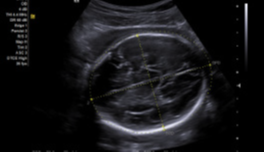

Syngo Auto OB

- 适用于产科和早孕检查类型

- 提供双顶径(BPD)、枕额径(OFD)、头围(HC)、腹围(AC)、股骨长图(FL)和肱骨长度(HL)的自动测量